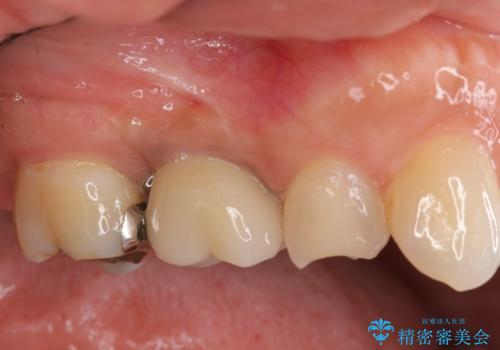

外科処置は一度だけ|抜歯即時インプラントで短期間で自然な見た目へ

前歯の変色が気になる〈セラミッククラウン〉

担当医 瀧村怜未